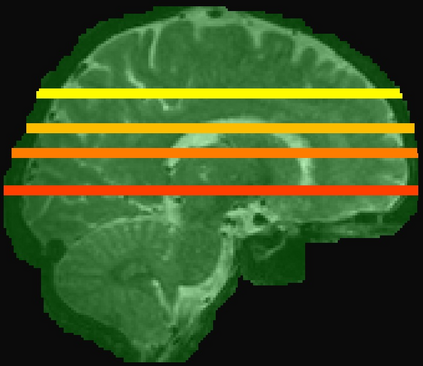

Imaging markers of cerebral small vessel disease provide valuable information on brain health, but their manual assessment is time-consuming and hampered by substantial intra- and interrater variability. Automated rating may benefit biomedical research, as well as clinical assessment, but diagnostic reliability of existing algorithms is unknown. Here, we present the results of the \textit{VAscular Lesions DetectiOn and Segmentation} (\textit{Where is VALDO?}) challenge that was run as a satellite event at the international conference on Medical Image Computing and Computer Aided Intervention (MICCAI) 2021. This challenge aimed to promote the development of methods for automated detection and segmentation of small and sparse imaging markers of cerebral small vessel disease, namely enlarged perivascular spaces (EPVS) (Task 1), cerebral microbleeds (Task 2) and lacunes of presumed vascular origin (Task 3) while leveraging weak and noisy labels. Overall, 12 teams participated in the challenge proposing solutions for one or more tasks (4 for Task 1 - EPVS, 9 for Task 2 - Microbleeds and 6 for Task 3 - Lacunes). Multi-cohort data was used in both training and evaluation. Results showed a large variability in performance both across teams and across tasks, with promising results notably for Task 1 - EPVS and Task 2 - Microbleeds and not practically useful results yet for Task 3 - Lacunes. It also highlighted the performance inconsistency across cases that may deter use at an individual level, while still proving useful at a population level.